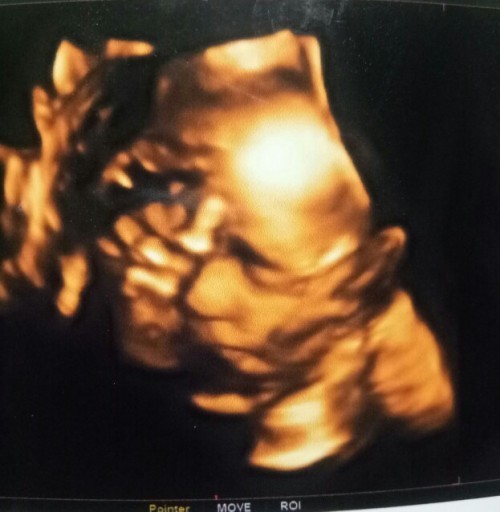

จ้ำม่ำน่าเอ็นดู😍